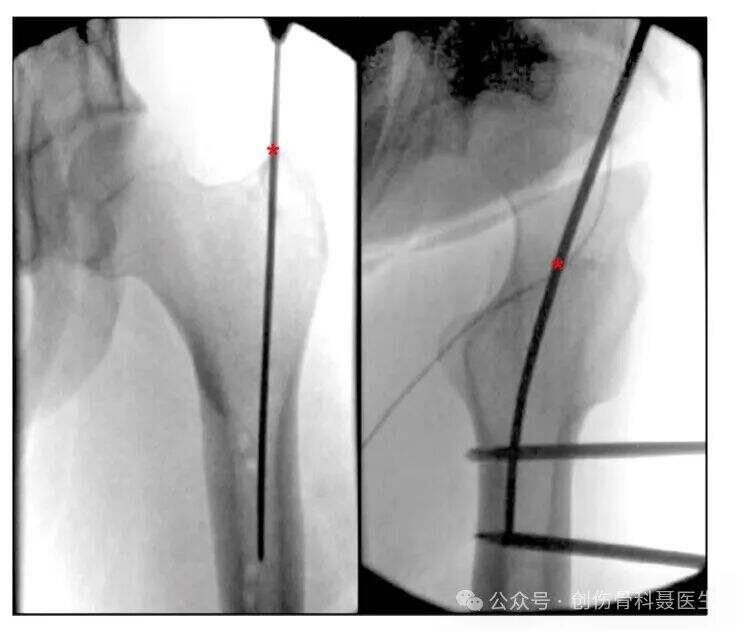

Insision & införingspunkt:

Intrådespunkt vid större trokantern: Intrådespunkten ligger vid spetsen av den större trokantern. På AP-bildet riktas den mot det mediala området av medullärkanalen; på laterala bilden är den justerad med centrum av trokantern och femoralkanalen. Intrådespunkten vid större trokantern används ofta hos överviktiga patienter, är tekniskt mindre krävande och kan vara förknippad med kortare operationslängd och lägre komplikationsfrekvens jämfört med intrådespunkten i piriformisfosset.

Intrådespunkt i piriformisfosset: Intrådespunkten ligger i piriformisfosset (depressionen medialt till den större trokantern, vid basen av femoralhalsen), vilket är fäststället för den yttre obturator-tendonen. Detta är den verkliga anatomiiska utgångspunkten som är justerad med femoralkanalen.